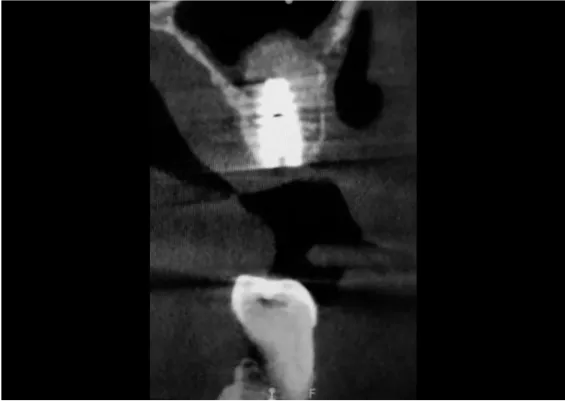

TRÓJWYMIAROWA REKONSTRUKCJA WYROSTKA ZĘBODOŁOWEGO PRZY UŻYCIU INDYWIDUALNIE DRUKOWANYCH SIATEK TYTANOWYCH YXOSS ReOss

To kolejna metoda umożliwiająca precyzyjną odbudowę zadanego kształtu tkanki kostnej przy użyciu standardowych materiałów kościotwórczych, kości własnej lub PRF oraz zewnętrznego rusztowania w postaci siatki z biozgodnego stopu tytanu. Siatka jest indywidualnie projektowana w technologii CAD CAM i następnie drukowana dla konkretnego przypadku.

Dotychczas stosowane stabilizatory zewnętrzne w formie siatek tytanowych używane do regeneracji kostnej lub w zabiegach odtwórczych w chirurgii szczękowo-twarzowej uwzględniały materiały ręcznie doginane i formowane podczas zabiegu operacyjnego. Zastosowanie technologii CAD CAM dla potrzeb druku materiałów przeznaczonych do indywidualnej rekonstrukcji kostnej znacznie poprawiło precyzję i jakość uzyskiwanych efektów. Wdrożenie biozgodnych stopów tytanu do druku siatek zdecydowanie ograniczyło odsetek powikłań zapalnych.

Precyzja projektu druku siatki bazuje na dokładności odwzorowania kształtu kości w stożkowej tomografii komputerowej CBCT, co zapewnia ich dobre przyleganie do podłoża kostnego oraz ogranicza powstawanie powikłań w postaci obnażania się siatek. Precyzja projektu oraz materiał, z którego wykonana jest siatka (biozgodny stop tytanu), powodują, że obnażenie się siatki nie zaburza procesu gojenia i regeneracji kostnej.